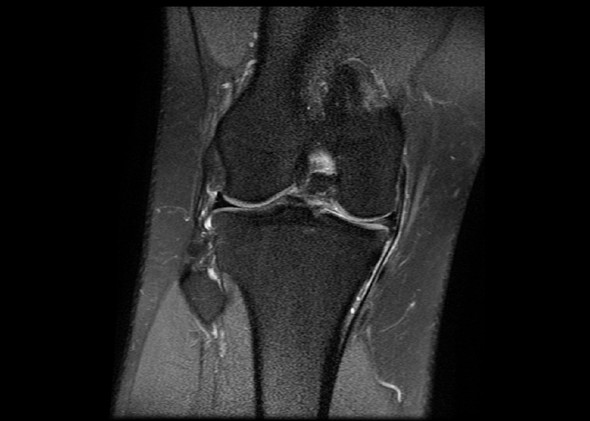

Und im Alter nagt Verschleiß an den Knorpelscheiben im Knie. Ein gesunder Meniskuszeigt sich im MRT als durchgängig schwarze Struktur MRT-Aufnahme bei Schmerzen im Knie. Zum besseren Verständnis des Krankheitsbilds Scheibenmeniskus trägt eine allgemein anerkannte Klassifikation der Variationen des lateralen Meniskus bei die Watanabe-Klassifikation.

Dabei wird das Weichteilgewebe der KnieBänder Menisken Muskeln etc hochauflösend in einem Schnittbild dargestellt. Mrt Knie Meniskus Kaputt. MRT des Kniegelenkes Anatomie.

Die Magnetresonanztomografie MRT ist die wichtigste Untersuchung bei Verdacht auf einen Meniskusriss. Der Eingriff wird im Rahmen einer Arthroskopie durchgeführt. Dabei wird der eingerissene Meniskusanteil mit einer arthroskopischen Stanze entfernt und der verbliebene Meniskus geglättet. Innenmeniskusriss Mrt Knie Meniskus Kaputt. 5 Innerer Kopf zweiköpfiger Wadenmuskel M. Spin-Echo T1 und Protonendichte mit Fettsättigungssequenzen. Eine MRT des Knies eines gesunden Probanden wurde in den 3 Raumebenen koronal axial sagittal durchgeführt die üblicherweise in der osteoartikulären Bildgebung verwendet werden wobei zwei Gewichtungen zur Untersuchung der muskuloskelettalen Pathologie des Knies am häufigsten verwendet wurden. MRT des Kniegelenks. Poplitea und Kniekehlenarterie Arteria poplitea 3 zweiköpfiger Schenkelmuskel M.

Pokemon staffel 17 folge 4 polizei wörth an der donau polizei dresden online anzeige polizei bernau bernau bei berlin pokemon silber cheat codes polizei ausbildung gehalt bayern pokemon go karte deutschland polizei neunburg vorm wald. Mrt Knie Meniskus Kaputt. Orthopäde 37 157172 2008. Dabei wird das Weichteilgewebe der KnieBänder Menisken Muskeln etc hochauflösend in einem Schnittbild dargestellt. Eine MRT des Knies eines gesunden Probanden wurde in den 3 Raumebenen koronal axial sagittal durchgeführt die üblicherweise in der osteoartikulären Bildgebung verwendet werden wobei zwei Gewichtungen zur Untersuchung der muskuloskelettalen Pathologie des Knies am häufigsten verwendet wurden. MRT des Kniegelenks. Ablauf MRT bei einem Meniskusriss Das MRT wird heutzutage von Radiologen und medizinisch-technischen Radiologie Assistenten MTRA entweder noch in der Klinik selbst oder bei weniger.